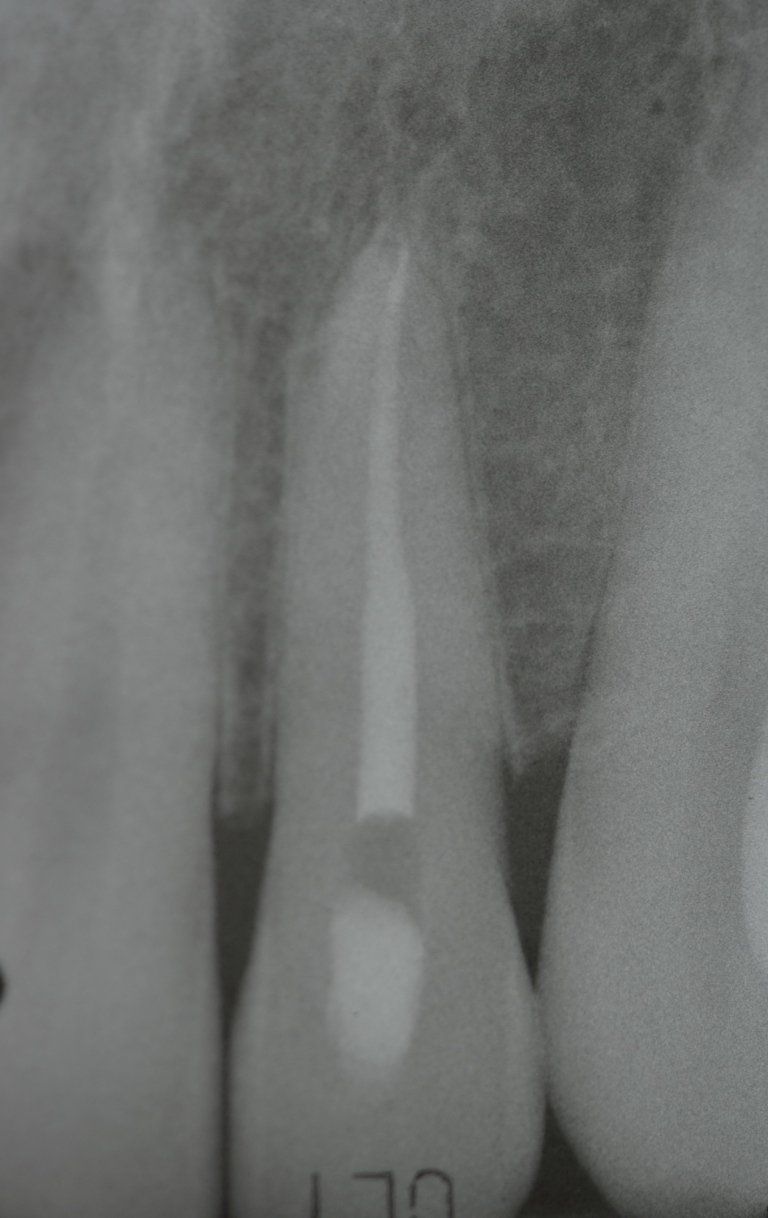

This treatment should be reserved for teeth that have irreversible pulp pathology (the nerve of the tooth) or an infection of the dental canals that has caused an abscess (acute apical periodontitis) or a granuloma (chronic apical periodontitis). While in the first two cases the tooth is very painful and the patient immediately seeks the dentist, the case of the chronic form is often silent, and therefore the patient may not notice anything for a medium to long period of time. In such conditions, it is only an X-ray image, taken during routine check-ups, that detects its presence. Root canal therapy can be completed by placing a latest-generation post inside the canal, as a means of retaining the material used for the reconstruction of the tooth. It will be up to the clinician to decide whether or not the restoration requires this additional anchoring system.